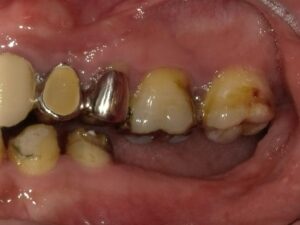

下顎大臼歯2本欠損症例

BEFORE AFTER 47歳男性/下顎1本欠損/インプラント埋込手術 【治療内容】 左下臼歯は元々ブリッジが入ってい…